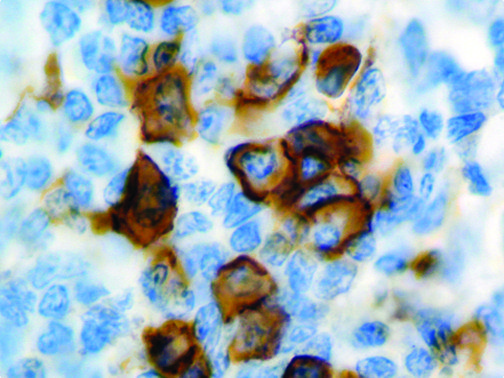

It is the ICU physician who is most likely to witness one of the deadliest manifestations of the abnormal immunological response, the cytokine storm syndrome (CSS). This response is also referred to by some as the cytokine release syndrome (CRS). CSS is characterized by continuous activation and expansion of macrophage and lymphocyte populations, which secrete large amounts of cytokines, causing the cytokine storm. This massive cytokine release is akin to hemophagocytic lymphohistiocytosis (HLH) disease, a syndrome characterized by initial unchecked and persistent activation of cytotoxic T lymphocytes and NK cells.

Clinical and laboratory manifestations of HLH include fever, enlarged liver and/or spleen, neurologic dysfunction, coagulopathy, liver dysfunction, cytopenias (i.e., low levels of erythrocytes, leukocytes, and/or platelets), hypertriglyceridemia, hyperferritinemia, hemophagocytosis, and eventually diminished NK cell activity as the immune system becomes progressively paralyzed. HLH can be familial (primary HLH) or secondary to another disease process (sHLH), such as rheumatic disease, in which it is referred to as macrophage activation syndrome (MAS, characterized by elevated ferritin).